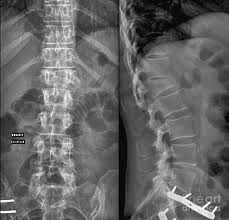

Picture frame vertebra in the largest biology dictionary online. Check out the pronunciation, synonyms and grammar. Browse the use examples 'picture frame vertebra' in the great english corpus. Enlarged vertebral body with reinforced peripheral trabeculae and more lucent center, typically in lumbar spine. Find & download free graphic resources for frame. ✓ free for commercial use ✓ high quality images. Radiographically diminished density of trabecular bone with relative preservation of the cortex, a sign of osteopenia. Frame picture photo camera border design photography gallery decoration. Free learning resources for students covering all major areas of biology. Free for commercial use no attribution required high quality images. Information and pictures of the spine and spinal cord showing c1 to s5 vertebra and which vertebra effect various body functions. Make a blurred photo frame online. The human spine is composed of 33 vertebrae that interlock.

Second example, with the blurred frame around photo of rose, made using all default settings, except. Browse the use examples 'picture frame vertebra' in the great english corpus. Radiographically diminished density of trabecular bone with relative preservation of the cortex, a sign of osteopenia. Almost files can be used for commercial. Check out our vertebrae pictures selection for the very best in unique or custom, handmade did you scroll all this way to get facts about vertebrae pictures? Picture frame vertebral body is a radiologic appearance in which the cortex of the vertebral body is thickened. Radiographs revealed a picture frame l1 vertebra which was deformed and enlarged with loss of normal alignment. Experiment with deviantart's own digital drawing tools.

Look at links below to get more options for getting and using clip art. We found one dictionary with english definitions that includes the word picture frame vertebra: This video describes some commonly asked vertebral appearances in neet pg exam. Find & download free graphic resources for frame. Things tagged with 'picture_frame' (675 things). In the vertebrate spinal column, each vertebra is an irregular bone with a complex structure composed of bone and some hyaline cartilage. Loonapix offers you a huge gallery to choose from. Learn vocabulary, terms and more with flashcards, games and other study tools. This sign can be seen in patients with paget disease. Browse the use examples 'picture frame vertebra' in the great english corpus. Picture frame vertebral body is a radiologic appearance in which the cortex of the vertebral body is thickened. Picture frame moulding for wood picture frames, wood moldings, picture frame wood, aluminium picture frames, wood veneer and bare wood mouldings. Check out the pronunciation, synonyms and grammar.

Second example, with the blurred frame around photo of rose, made using all default settings, except. This video describes some commonly asked vertebral appearances in neet pg exam. Experiment with deviantart's own digital drawing tools. ✓ free for commercial use ✓ high quality images. Radiographs revealed a picture frame l1 vertebra which was deformed and enlarged with loss of normal alignment. This sign can be seen in patients with paget disease. Check out our vertebrae pictures selection for the very best in unique or custom, handmade did you scroll all this way to get facts about vertebrae pictures? Radiographically diminished density of trabecular bone with relative preservation of the cortex, a sign of osteopenia.

A 73 yo man comes to. Information and pictures of the spine and spinal cord showing c1 to s5 vertebra and which vertebra effect various body functions. Original file at svg format. Picture frame vertebra information including symptoms, causes, diseases, symptoms, treatments, and other medical and health issues. Loonapix offers you a huge gallery to choose from. The human spine is composed of 33 vertebrae that interlock. Picture frame vertebra in the largest biology dictionary online. Picture frame vertebral body is a radiologic appearance in which the cortex of the vertebral body is thickened. Radiographically diminished density of trabecular bone with relative preservation of the cortex, a sign of osteopenia. Click on the first link on a line below to go directly to a page where picture frame vertebra is defined. Free learning resources for students covering all major areas of biology. Second example, with the blurred frame around photo of rose, made using all default settings, except. Select a picture on your computer or phone and then click ok.